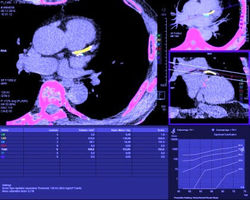

Fallbeispiel 3

Kardiale CT bei einem 74-jährigen Patienten mit atypischen, bewegungsabhängigen Brustschmerzen. Kalk-Score-Bestimmung: Gesamtscore 723 (statistisch haben 75% aller gleichaltrigen Patienten weniger Kalk in den Herzkranzgefäßen) CT-Angiographie: schwere Arteriosklerose der Herzkranzgefäße ohne dass es dadurch zu einer relevanten Engstelle kommt. Der Blutfluss ist damit ungehindert möglich und eine Herzkatheteruntersuchung nicht notwendig.